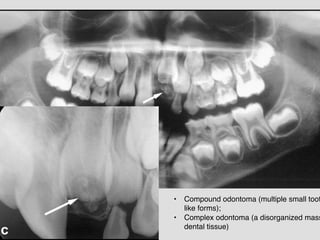

• Compound odontoma (multiple small toot

like forms);!

• Complex odontoma (a disorganized mass

dental tissue)